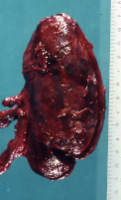

Die Abbildung 10 zeigt den Gefäßabbruch der Art. hypogastrica links bei Abstosungsreaktion der implantierten Niere und die Abbildung 11 das explantierte Organ